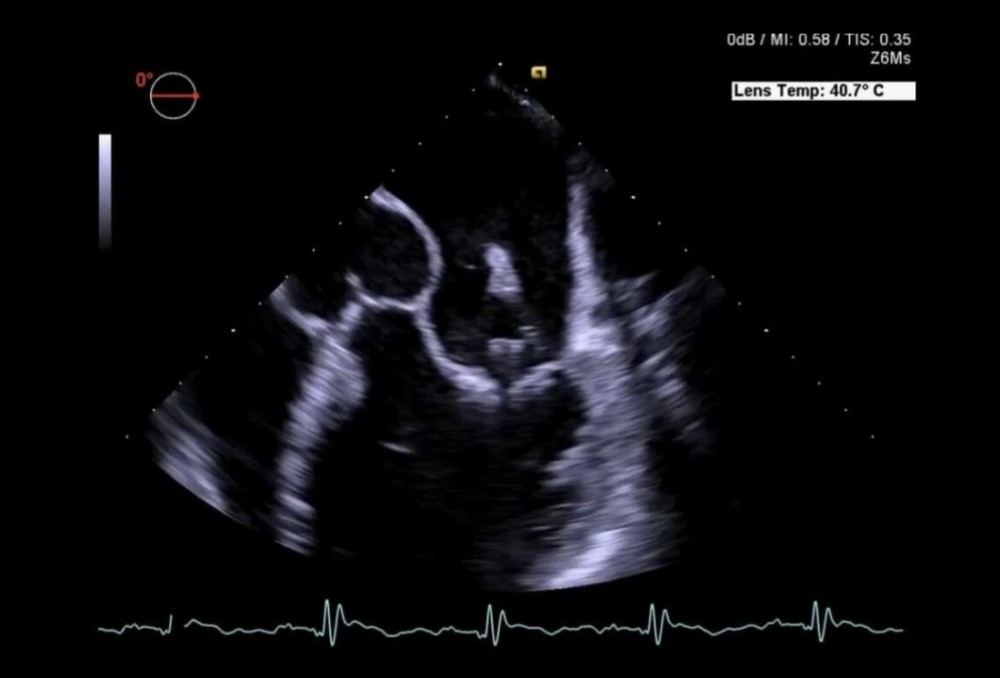

Z6Ms — 4D real vaxt TEE

Z6Ms TEE tam həcmli 3D qabiliyyətlə (bəzən ayrıca sayılır)